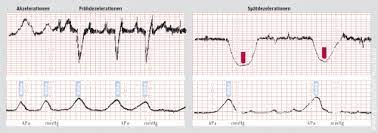

Ab wann brauche ich ein ctg? Verläuft die geburt normal, reichen jede stunde 10 bis 20 minuten völlig aus. Die antwort verrät ein schwangerschaftstest. Das ctg zeichnet jegliche wehentätigkeit auf, demnach lassen sich im ctg auch übungswehen erkennen. Je nach größe des abfalls, synchronität mit wehen und dauer der dezelerationen unterscheidet man dabei verschiedene stufen.

Je nach größe des abfalls, synchronität mit wehen und dauer der dezelerationen unterscheidet man dabei verschiedene stufen. Jutta2 schrieb am 06.08.2010 19:58 registriert seit 28.05.06 beiträge: Denn mit einer ctg lassen. Zur differenzierung zwischen übungswehen und „echten wehen, die eine geburt ankündigen, lassen sich im ctg verschiedene hinweise finden. Bei einer risikoschwangerschaft, vorzeitigen wehen oder anderen problemen kann das ctg auch schon vor der 30. Bei jeder frau fühlen sich wehen anders an. Ab wann und wie häufig ein ctg gemacht wird, hängt grundsätzlich vom verlauf der schwangerschaft ab. Übungswehen treten nicht so regelmäßig auf, wie geburtsvorbereitende wehen.

Je nach größe des abfalls, synchronität mit wehen und dauer der dezelerationen unterscheidet man dabei verschiedene stufen.